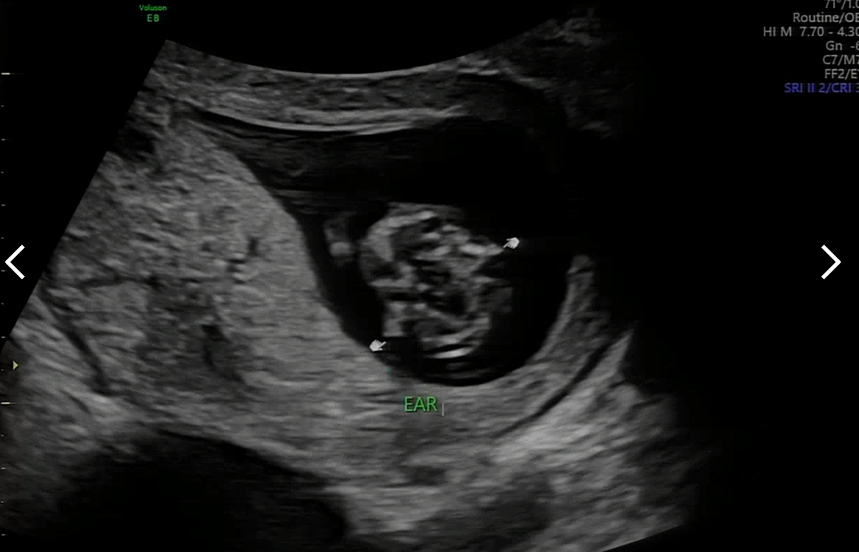

12주차 벌써 네 번째 산부인과 방문. 원장님도 이젠 얼굴을 보면 반겨주신다. 이 날은 1차 기형아 검사와 정말 초음파 검사가 있는 날. 병원에 약 15분 정도 일찍 가야 했고 원장님이 아닌 초음파 선생님께서 약 12분에 걸쳐서 초음파를 꼼꼼히 봐주셨다. 눈으로 봐도 훨씬 커져 있는 우리 아기.

1차 정말 초음파에서 가장 중요한건 태아 목덜미 투명대 측정. NT로 표기되는데 이 수치가 3mm 이상이면 고위험군으로 보고 기형 위험이 높다고 판단한다. 투명대가 3mm가 넘는다고 무조건 기형아라는 건 아니고 추가 검사를 통해 아이의 기형 유무를 더 면밀히 판단해야 한다. 다행히 우리 아기는 1.23mm가 나와 정상범위였다. 아이가 건강하기만 해도 행복이라더니 이렇게 정상 범위의 수치가 나오면 정말 감사하고 마음이 놓이는 거 같다.

정말 초음파이기 때문에 이 주수에 볼 수 있는 다양한 신체 기관의 발달 정도를 보여주셨다. 여긴 귀라며 ㅎㅎ